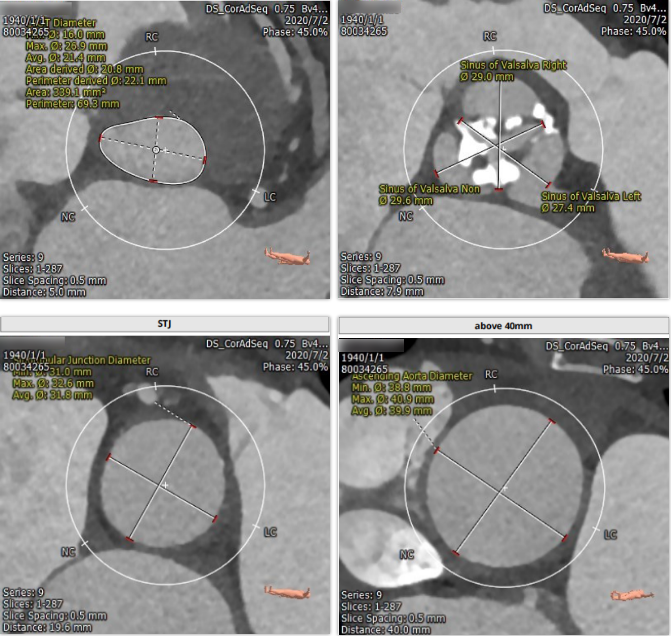

主动脉根部解剖

三叶瓣,重度钙化,左冠开口位置低4.2mm,右冠开口较高15.0mm。法式窦结构大小可,左心室大小尚可,心肌肥厚,升主动脉未见明显扩张,股动脉直径均可。

三叶瓣,重度钙化。左冠 4.2mm 右冠 15mm, sinus:29mm。此病例难点在左冠开口很低,仅4.2mm,窦的结构不大,瓣叶较为冗长。该患者左冠开口低,冠脉堵闭风险高。拟予术中进行左冠保护,20mm球囊扩张,左冠切线位观察瓣叶和冠脉开口相对关系。选择VenusA-Valve L23瓣膜植入。